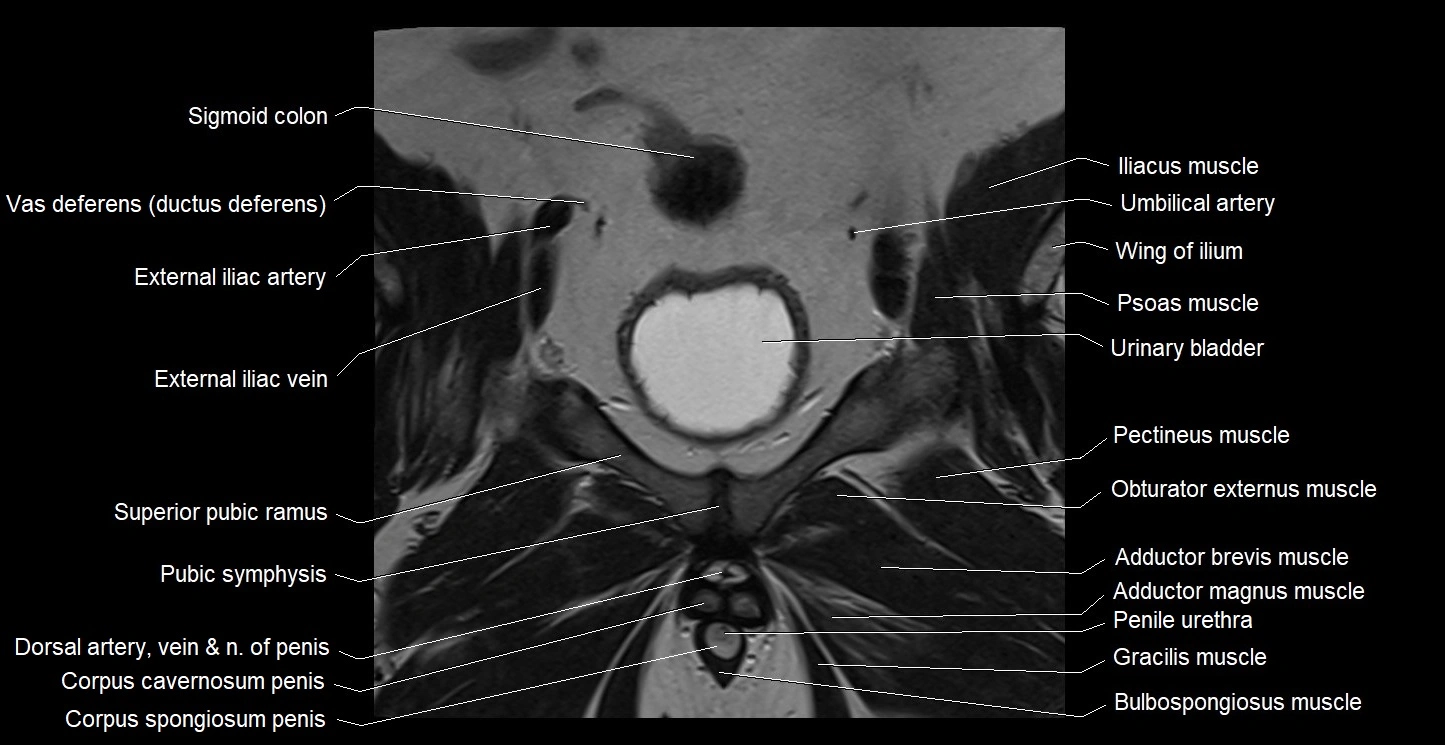

- Adductor brevis muscle

- Adductor magnus muscle

- External iliac vein

- Gracilis muscle

- Obturator externus muscle

- Pectineus muscle

- Penile urethra

- Pubic symphysis

- Sigmoid colon

- Superior pubic ramus

- Umbilical artery

- Urinary bladder